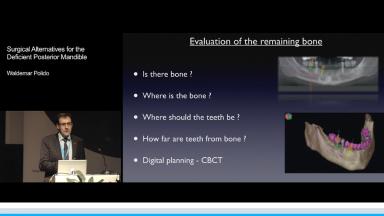

The rehabilitation of posterior mandible with dental implants represents a difficult challenge for clinicians due to the lack of supporting bone. The alveolar nerve presence and the gradual vertical and horizontal resorption of the mandibular bone crest in both partially and totally edentulous patients can be treated by several surgical options - vertical ridge augmentation, surgical displacement of the inferior alveolar nerve, or the placement of short implants (8 mm or less).

This lecture presents the different surgical techniques currently being used to vertically augment the posterior mandible: guided bone regeneration (GBR), alveolar distraction osteogenesis, and onlay bone grafting; however, few of these techniques have been tested in a randomized clinical trial (RCT), and some bone augmentation techniques are complicated by an unpredictable resorption of the grafted material.